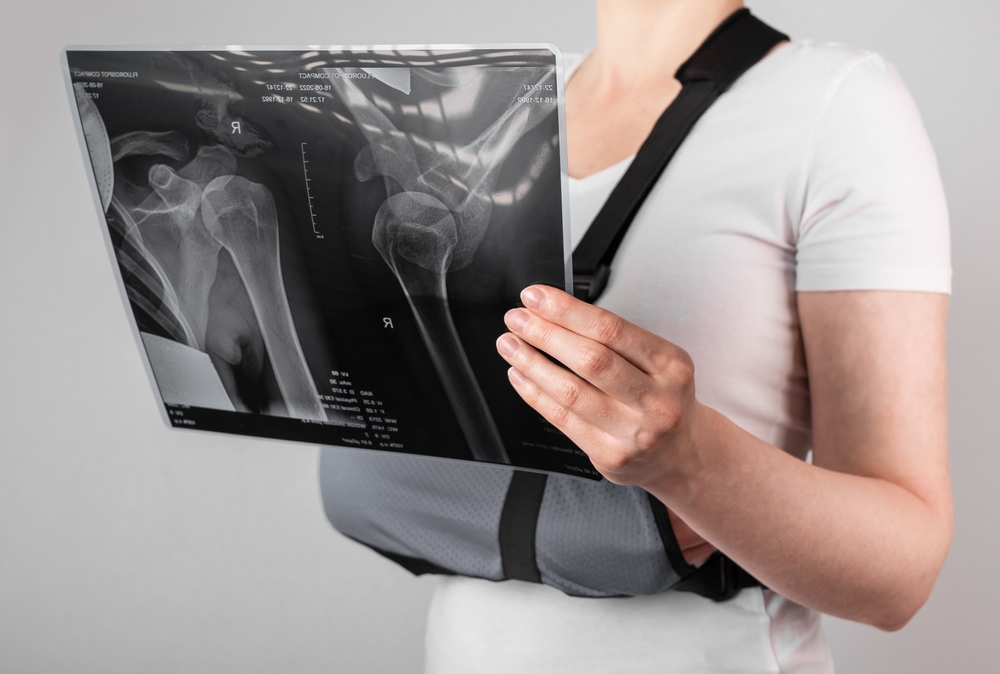

Lesões de ombro no crossfit: conheça os tipos e como evitar!

Por ser bastante exigida durante os exercícios, as lesões de ombro podem ser comuns entre os praticantesCriado pelo americano Greg Glassman...